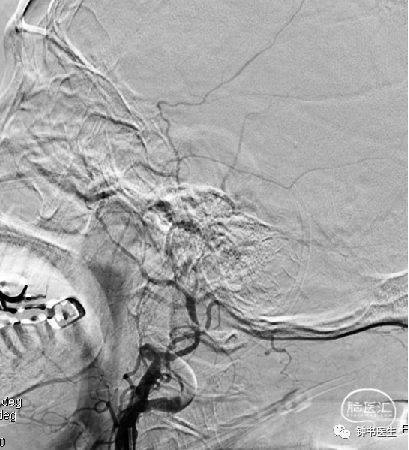

病例1

56y,意识不清伴右侧肢体无力5小时,GCS8分

再灌注损伤(出血):需降压

出血疼痛、烦躁,血压高

镇静镇痛影响神志观察

2012-11-8 CT

左颞部脑梗加重,出血渗出点增多。继续加强镇静镇痛治疗。

2012-11-10 CT

病情趋稳定,转出监护室治疗。